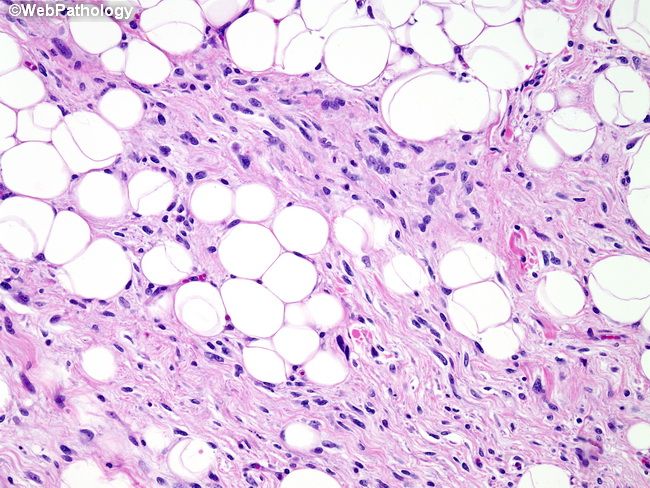

Фото Липосаркомы Мягких 114 фото